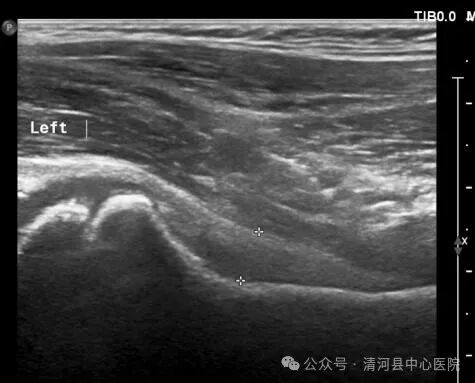

2、关节囊肿胀型:患侧股骨颈颈前间隙较健侧增宽大于1mm,或者整个关节囊厚度大于5-7mm,内回声欠均匀,关节囊与髂腰肌之间的界面凸面向前。